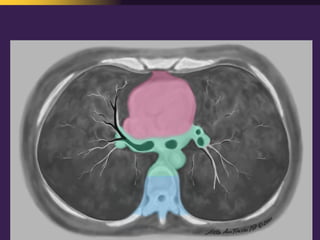

This document discusses mediastinal pathology using a compartmental approach. It describes the anatomy of the mediastinum and divides it into anterior, middle, and posterior compartments. Each compartment contains different structures and has a characteristic distribution of lesions. For example, 50% of lesions occur in the anterior compartment, which contains the thymus. The thymus is the most common site of lesions in the anterior compartment. Thymomas are the most common epithelial tumors of the thymus and mediastinum.